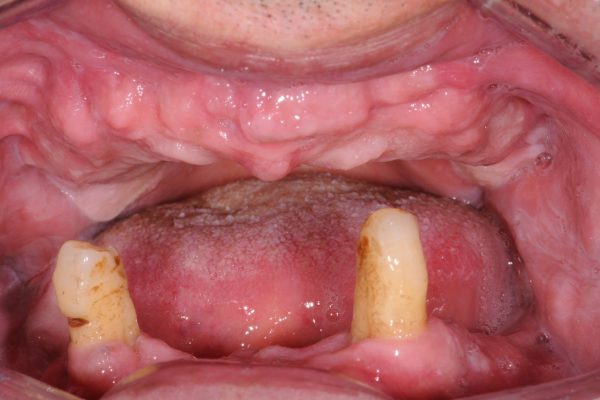

Anche in casi estremamente complessi, la riabilitazione Implanto-protresica , se ben pianificata, può dare dei risultati soddisfacenti, sia dal punto di vista estetico che funzionale.Scopri di più